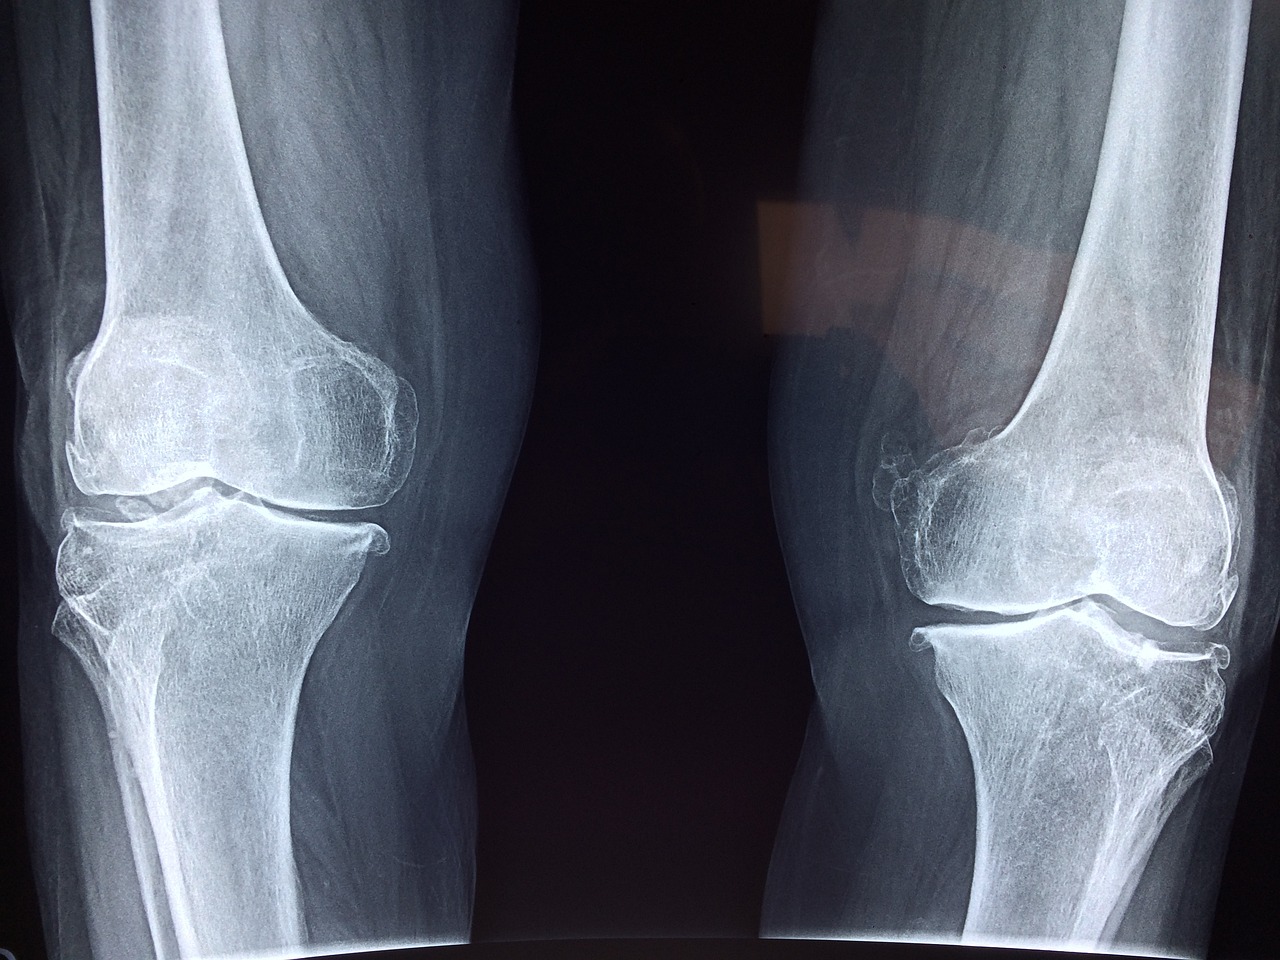

무릎 관절은 우리 몸에서 가장 많은 부담을 받는 부위 중 하나입니다. 걷기, 뛰기, 앉았다 일어나기 등 일상적인 활동에서 지속적으로 사용되기 때문에 무릎 건강이 악화되면 생활의 질이 크게 떨어질 수 있습니다.

꾸준한 관리가 필요하며, 관절에 통증이 있다면 전문의 상담 후 적절한 치료와 예방을 병행하는 것이 중요합니다. 건강한 무릎을 유지하여 활기찬 삶을 즐기시길 바랍니다!